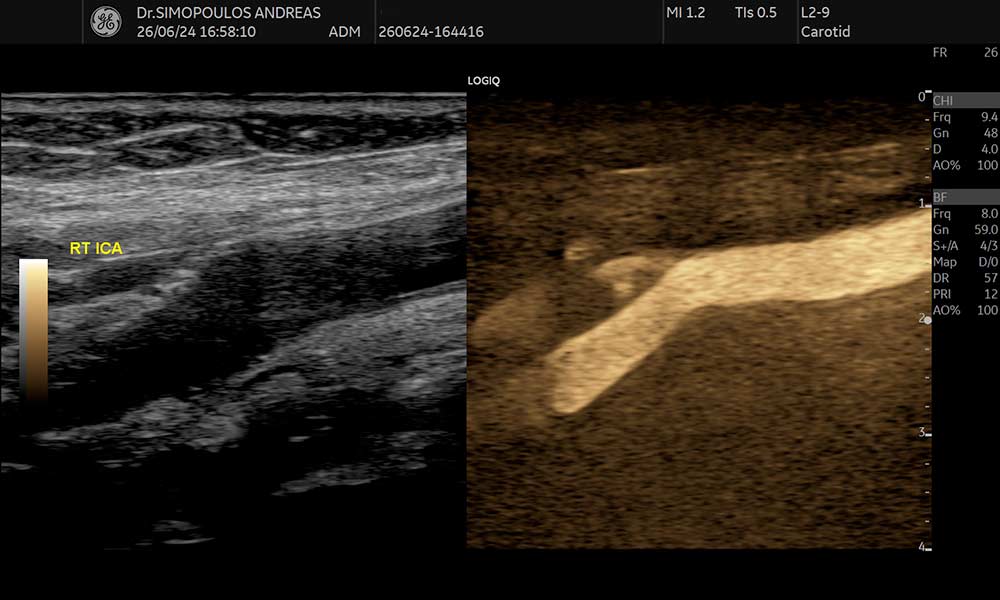

- Καρωτίδων και σπονδυλικών αρτηριών